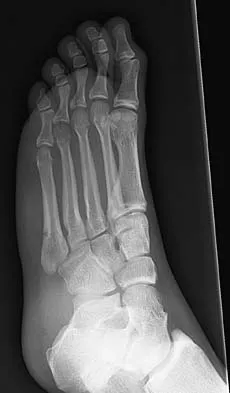

An active 47-year-old woman with rheumatoid arthritis reports forefoot pain and deformity and has difficulty with shoe wear. Examination reveals hallux valgus and claw toes. A radiograph is shown in Figure 10. What is the most appropriate surgical treatment?

Explanation

Rheumatoid arthritis commonly affects the metatarsophalangeal joints, which become destabilized with time resulting in hallux valgus and dislocated lesser claw toes. The result is metatarsalgia as the dislocated claw toes "pull" the fat pad distally. Severe hallux valgus reduces first ray load, which compounds the metatarsalgia because the load is transferred to the lesser metatarsal heads. First metatarsophalangeal arthrodesis restores weight bearing medially and corrects the painful bunion. Metatarsal head resection slackens the toe tendons to allow correction of the claw toes by whatever means necessary and decreases plantar load over the forefoot. Rheumatoid arthritis in the first metatarsophalangeal joint will continue to progress if osteotomies or a Lapidus procedure are performed. Keller resection arthroplasty increases transfer metatarsalgia and reduces push-off power during gait. Flexor-to-extensor tendon transfer of the lesser toes does not address the metatarsalgia and does not correct the dislocation of the metatarsophalangeal joint. Coughlin MJ: Arthritides, in Coughlin MJ, Mann RA (eds): Surgery of the Foot and Ankle, ed 7. St Louis, MO, Mosby, 1999, p 572.